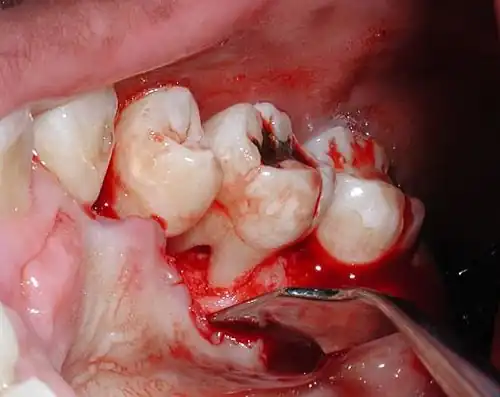

Bone loss from aggressive periodontitis that led to an exposed furcation on an upper molar. In health, the bone exists about a millimeter and a half away from the cementoenamel junction, which is the line that separates the crown from the root trunk (the line can be seen clearly in the photo).